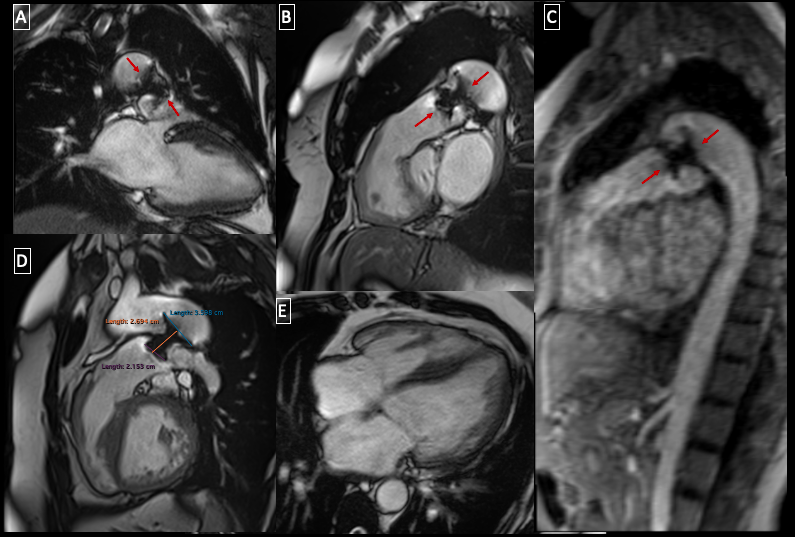

Fig. 1 Magnetic resonance imaging study. A) Left 2-chamber view showing the ductal occluder device (red arrows) with slight protrusion into the origin of the left pulmonary artery. B) Right ventricular outflow tract demostrating the position of the occluder device. C) Distal aortic arch and decending aorta with the device partially protuding into the aortic lumen. D) Dimensions of the occluder device. E) Four-chamber view demostrating left ventricular dilation.